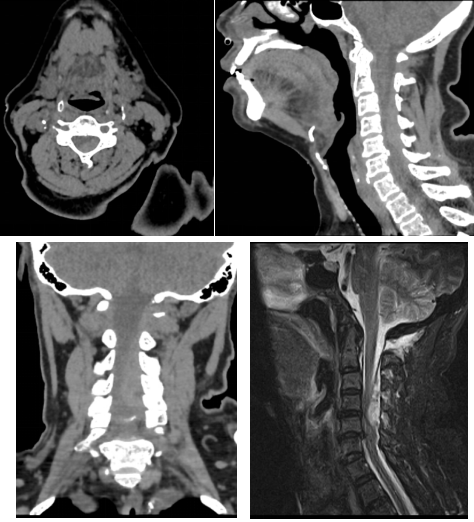

術(shù)前頸椎CT和磁共振:可見明顯血腫占位

通訊員符得紅報道:近日,63歲譚女士因“頸部疼痛伴左側(cè)肢體癱瘓2小時”聯(lián)系120后被送至我院脊柱外科,完善頸椎CT、磁共振后考慮“頸椎管內(nèi)出血并頸髓損傷”。體查:頸部活動疼痛受限,左側(cè)肢體肌力約Ⅱ級,右側(cè)肢體肌力正常。既往有“高血壓”、“糖尿病”、“心臟病”病史,3年前在外院行“冠脈支架植入”,術(shù)后一直口服“抗凝藥物”抗凝治療。